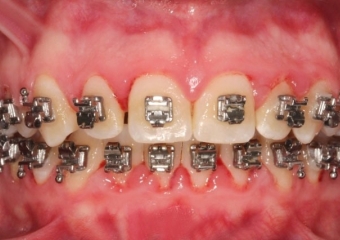

Mordida inicial